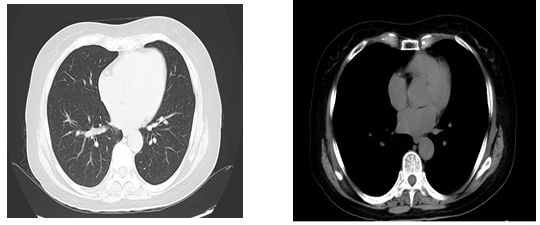

入院第7天双肺CT结果

提示:双肺间质改变,双侧胸腔积液,左肺下叶索条影

血气分析:氧分压63.4mmhg,氧饱和度93%,PH7.45